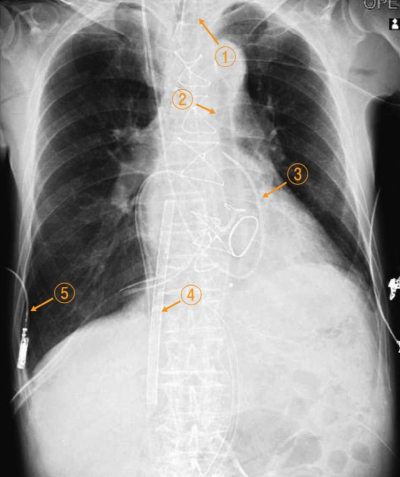

69歳の男性。心臓弁膜症手術直後で手術室に入室中である。循環動態が不安定であったため経皮的心肺補助<PCPS>と大動脈内バルーンパンピング<IABP>が留置されている。手術室を退室する前に撮影した胸部エックス線写真を別に示す。

肺動脈カテーテルはどれか。

a. ①

b. ②

c. ③

d. ④

e. ⑤